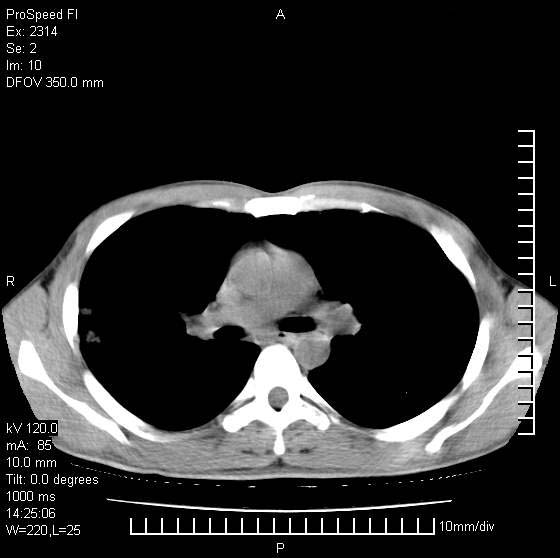

男性,再生障碍性贫血,入院前发热10天,最高40c,右侧胸痛,外院ct示右上,中肺边缘模糊的球性影(就是我现在图中标示的范围),考虑炎症,在我院使用头孢呋辛,洛美沙星10天,高烧消退,自感下午稍有发热,但今天ct示右上,中肺病灶明显扩大,还是考虑炎症,看其中的球型影是否霉菌感染??,是否能排除结核?